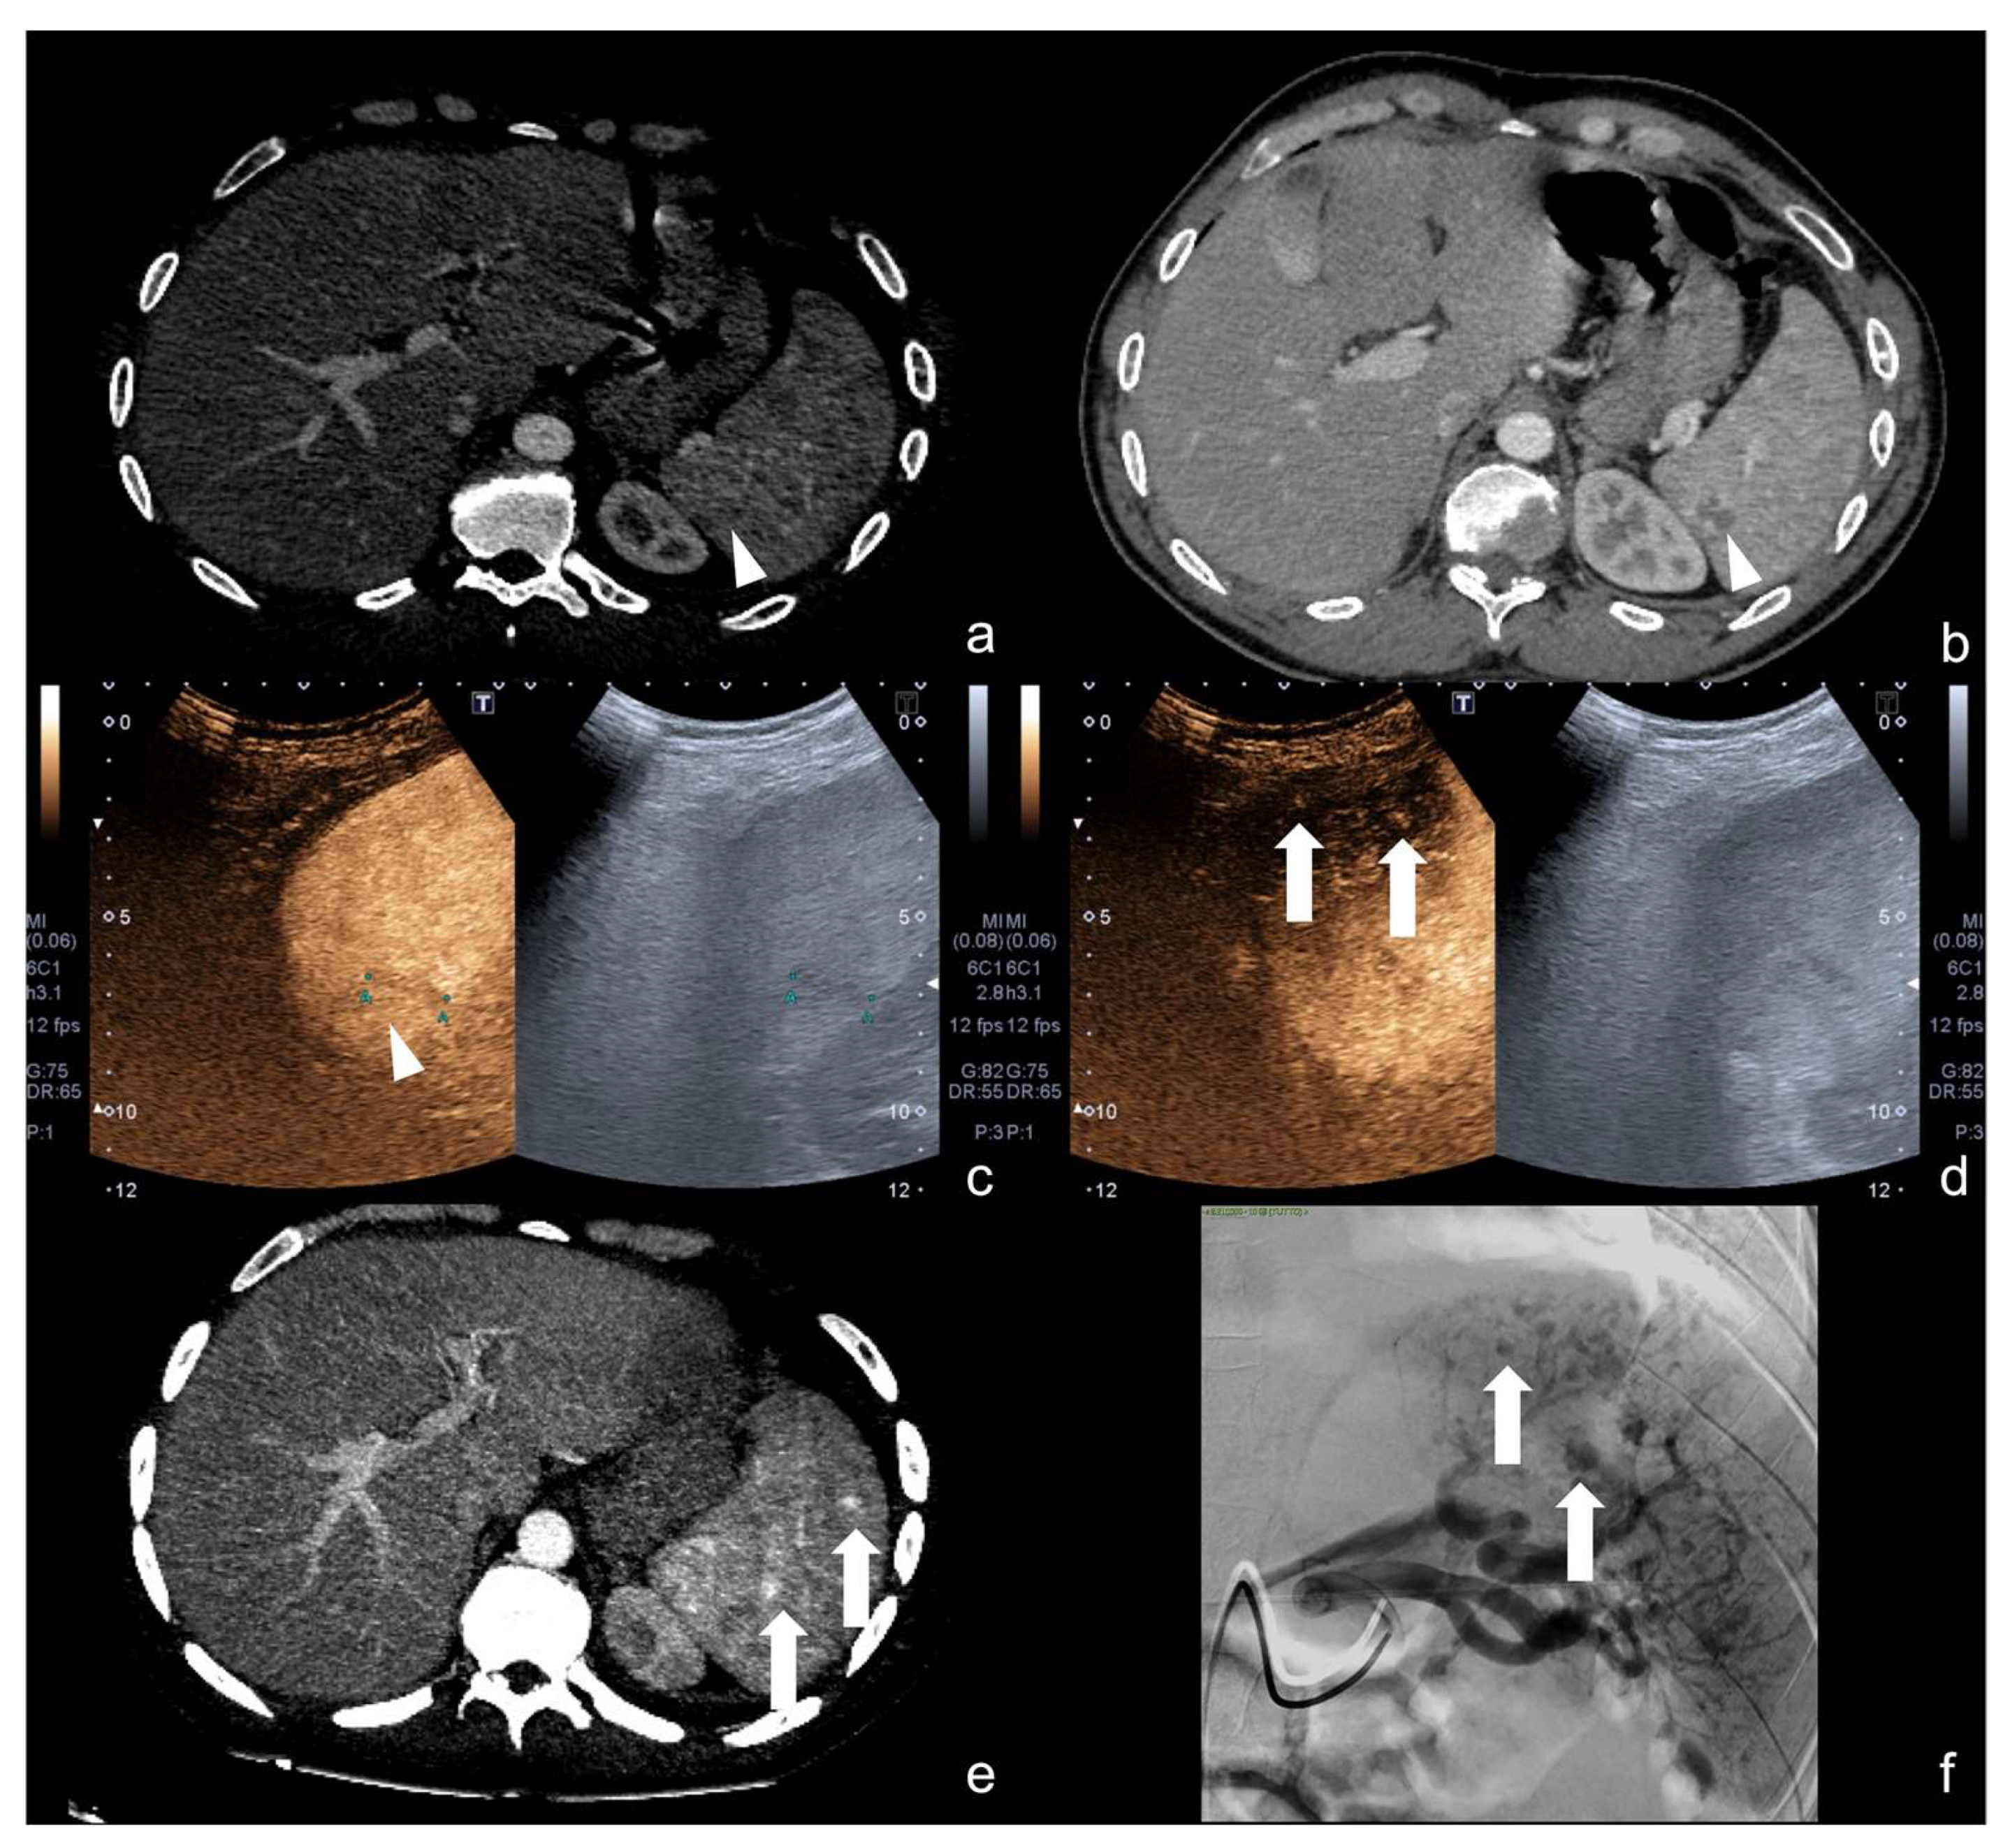

4.4. Step 4

Beware of lacerated areas of the parenchyma (pseudo-nodular spared area). Always integrate with a preliminary CD–US study before CEUS examination (Figure 26).

Figure 26.

An example of possible pitfall at CEUS performed to follow-up a parenchymal laceration; in this case, a hepatic laceration. At CEUS examination, a nodular area of enhancement was visible within the hepatic laceration (a, dotted arrow), suspected for PSA; however, this finding was inconsistent with the preliminary CD–US evaluation, because the hepatic laceration area did not show any vascular pattern of PSA inside (b, white arrowhead). This finding was suspected for pseudo-nodular spared hepatic parenchyma and confirmed at biphasic contrast-enhanced CT examination (c, arterial phase, white arrow; d, venous phase, white arrow).

4.5. Step 5

Beware to the growing parenchymal collections in the suspicion of a vascular, biliary, or urinary leak (Figure 27).

Figure 27.

Post-traumatic laceration of the left hepatic lobe (a, white arrowhead) with evidence of surgical packing (asterisk); after surgical lobectomy, contrast-enhanced CT scan (b) showed a small fluid collection close to the biliary duct clipping (white arrow). Such collection increased in volume at follow-up CEUS examinations (c,d, respectively, 2 and 3 weeks after surgery, white arrows); this finding indirectly suggested a possible biliary leakage, although not directly viewable at CEUS (c,d, white arrows). This finding was confirmed at post-contrast hepatospecific phase fat-sat T1w MRI examination that showed biliary leak (e, arrowheads). Subsequent exclusion of the biliary leak with complete reabsorption of the biliary collection at CT examination (f, arrow).